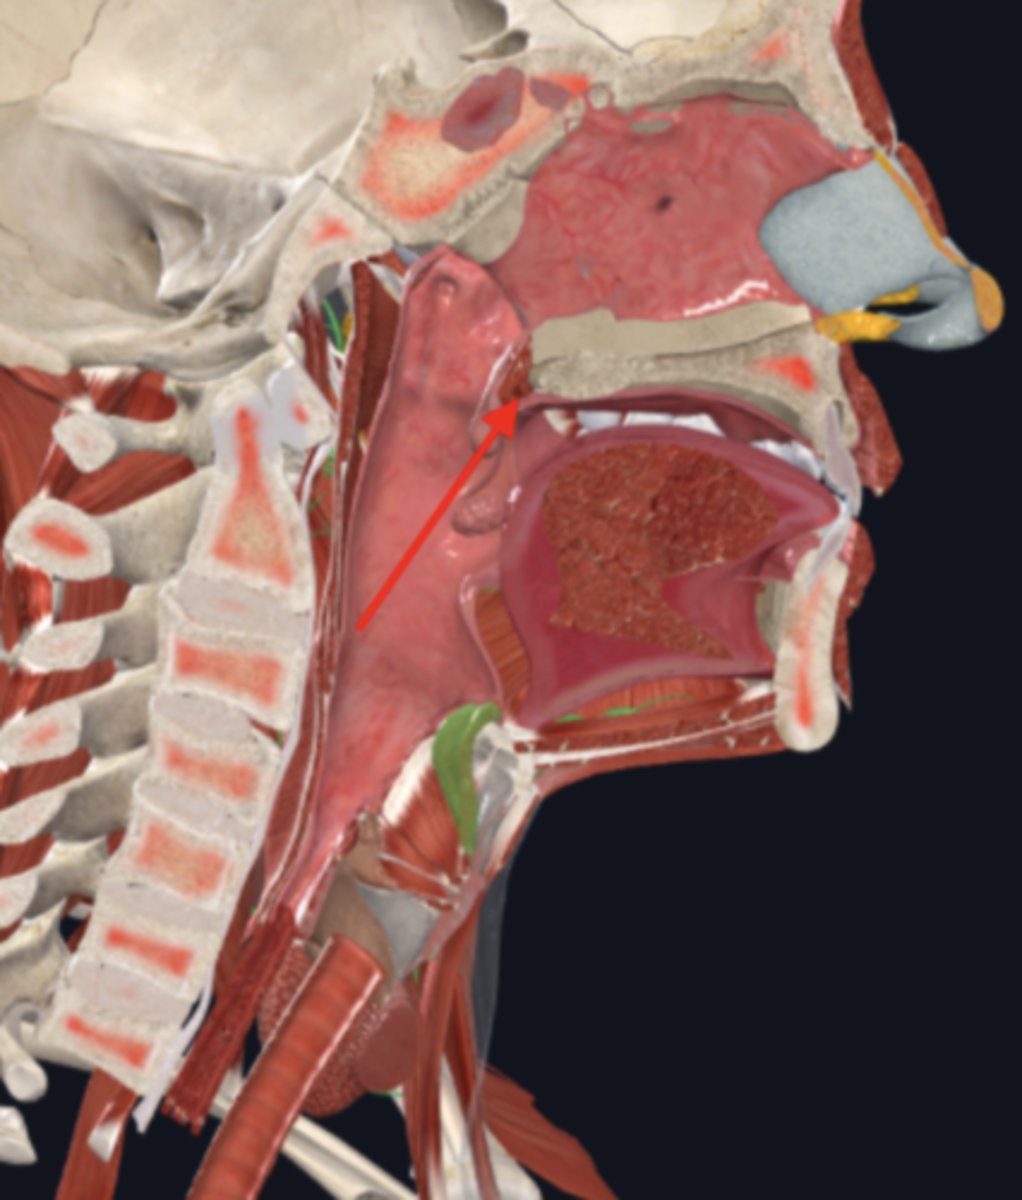

nasopharynx

name the circled region

oropharynx

name the circled region

laryngopharynx

name the circled region

epiglottis